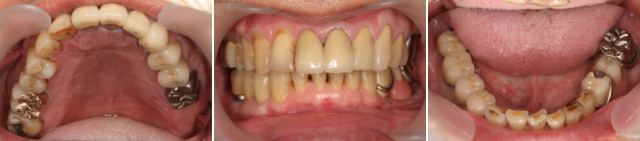

矯正で咬み合わせの治療を行った後に、歯周病治療と冠の作製に移り治療が完了しました。その後、メインテナンスに移行しました。治療して3年が過ぎましたが、どこも腫れることなく健康を維持されています。患者さんには、治療後とても喜んでいただきメインテナンスをキャンセルされたことはありません。

治療した状態が長く持って、安定していることが患者さんと診療室のゴールと考えています。